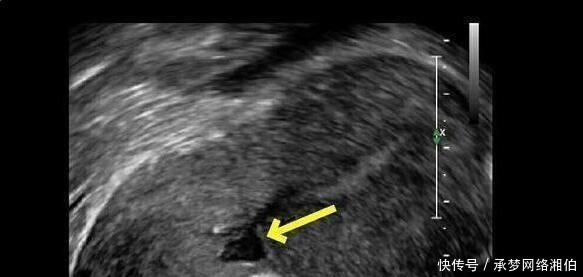

越多,剖腹产,因为它是剖腹产切口憩室”的发生率越高,风险越高。2.前置胎盘和胎盘植入剖宫产术后再次怀孕时,前置胎盘和胎盘植入的可能性会更高,如果胎盘完全密封的宫口,属于危险的前置胎盘,风险是非常高的。越高越危险,剖腹产如果剖腹产三四次,所以大部分发生在怀孕后胎盘植入。怀孕和生育后期,容易出血,风险是非常高的。3.重复剖腹产可能会导致子宫切口的位置弹性,不耐受拖船等到怀孕后,随着妊娠的增加,胎儿越来越大,子宫可以扩展,狭缝薄,一旦有点宫缩,可能使可怜的弹性和很薄的切口断裂,导致子宫破裂,胎儿证明不可能的,不仅会危及孕妇的生命,甚至切除子宫,4.操作更加困难剖腹产更重要的是,越难操作,风险也更高。【 胎盘|剖腹产最多剖几次?第3次剖腹产危险大吗?这些答案孕妇得搞清楚】